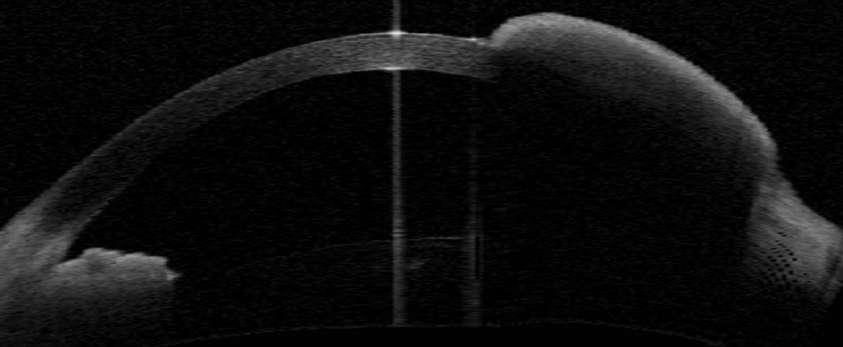

ü Angiografía con fluoresceína en la membrana MNVC Tipo Ia (DEP fibrovascular): se caracteriza por presentar área hiperfluorescente irregular visible desde un tiempo arteriovenoso precoz que incrementa la fluoresceina en tiempos tardíos con poca o nula difusión

2.G. MEMBRANA NEOVASCULAR COROIDEA (MNVC)

Clement F . “Angiografía”. Diagnóstico por la imagen en la retina, Sociedad Española de Retina y Vítreo, editado por Ignasi Jügens, Elservier, 2014, pp 41-66 Juan Verdaguer, T. (2010). Degeneración macular relacionada a la edad. Revista Médica Clínica Las Condes, 21(6), 949–955. doi:10.1016/s0716-8640(10)70620-9

A B